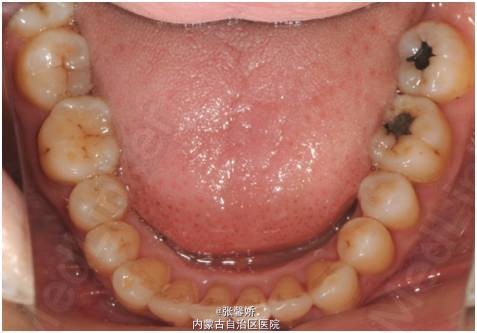

查体 辅查

上中线右偏1mm,A2、D4反合,A2、B2畸形牙偏小,拥挤度上颌4mm、下颌6mm。Spee曲线:左侧3mm,右侧2.5mm